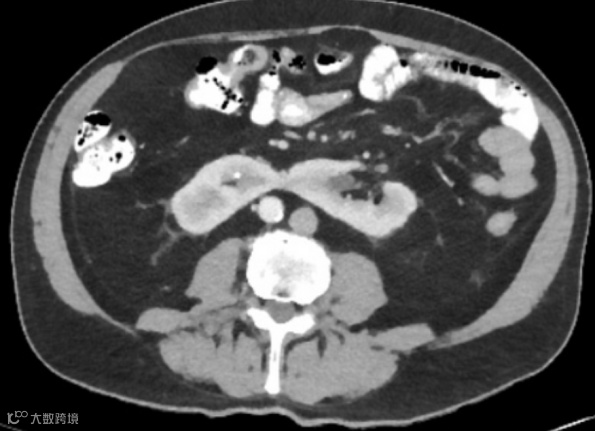

男,75岁,无痛性血尿。CT增强扫描提示马蹄肾合并肾峡部后下缘、中线左侧肿块,肿块切除后组织病理学检查显示为嗜酸细胞瘤。

肿瘤:马蹄肾患者肾细胞癌和肾盂癌的发病率略高于正常人群。

CT是发现马蹄肾并发症的最佳工具: